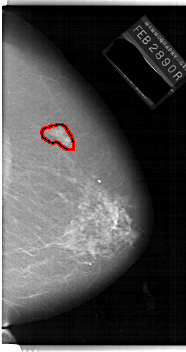

FILE: A_1144_1.RIGHT_CC.OVERLAY

TOTAL_ABNORMALITIES 1

ABNORMALITY 1

LESION_TYPE MASS SHAPE IRREGULAR MARGINS ILL_DEFINED

ASSESSMENT 4

SUBTLETY 4

PATHOLOGY MALIGNANT

TOTAL_OUTLINES 1

BOUNDARY